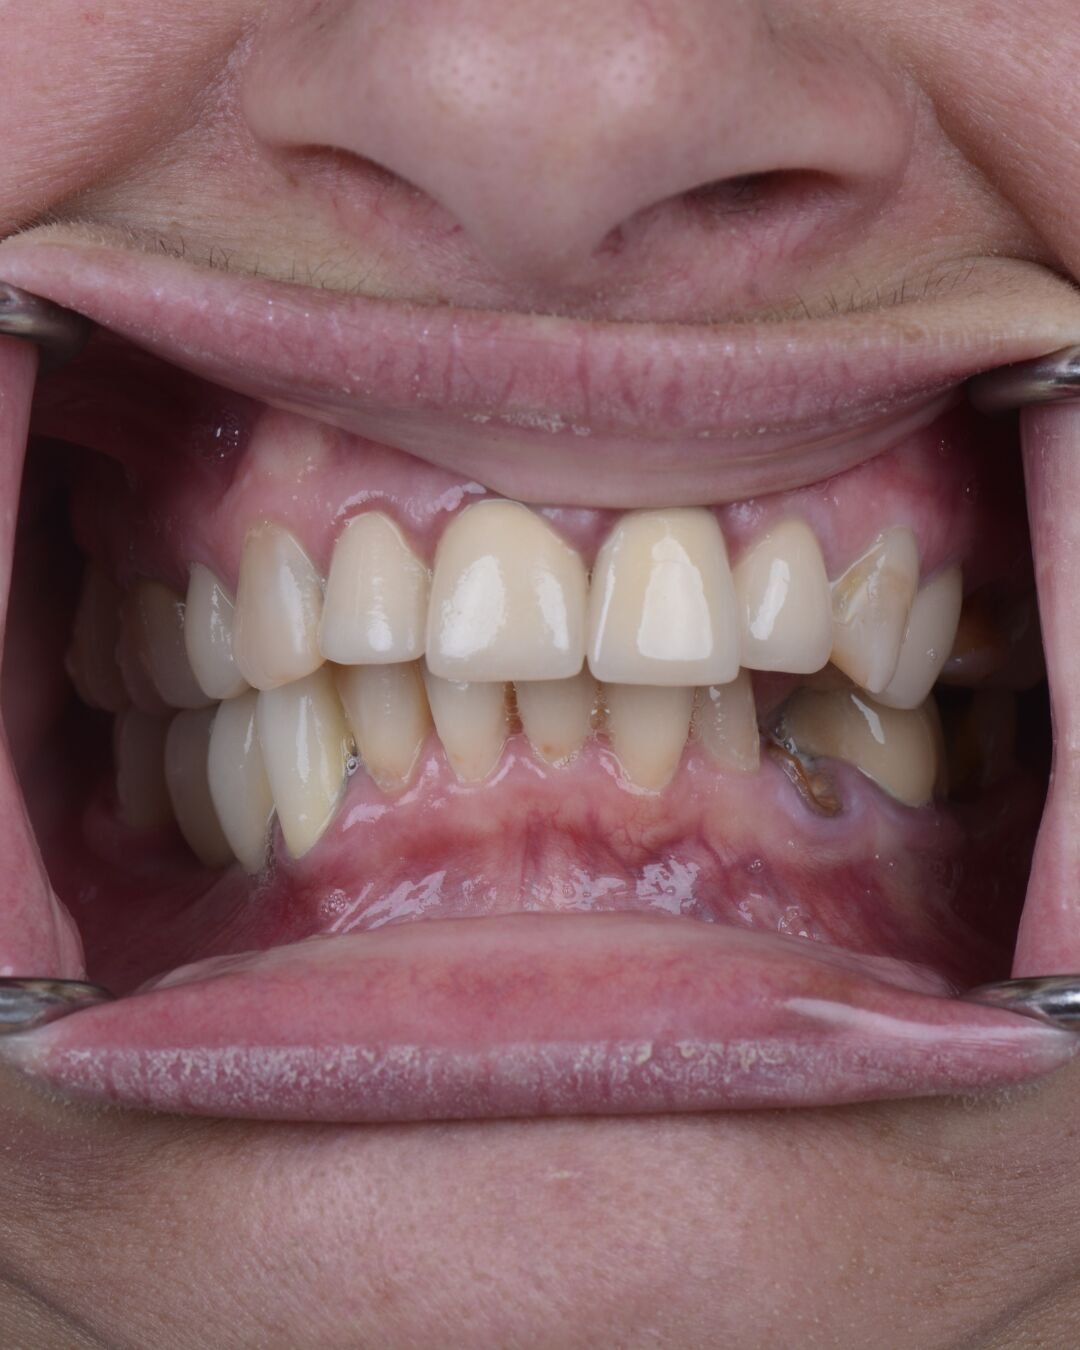

Real Smile Transformations

See the life-changing results from real patients who chose Fusion Dental Implants.